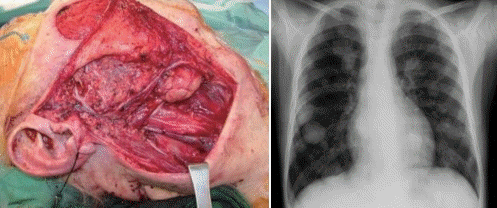

문 1. 10년 전 다음과 같은 수술을 받은 55세 남자 환자가 chest PA상 다음과 같은 소견이 관찰되었다. 가장 가능성이 있는 진단은?

① Adenocarcinoma

② Adenoid cystic carcinoma

③ Squamous cell carcinoma

④ Carcinoma ex pleomorphic adenoma

⑤ Acinic cell carcinoma

문 1. 답 ②

해 설 Adenocarcinoma: 25%-55%에서 원격전이가 발생할 수 있으며 특징적으로 폐나 뼈에 원격전이가 많이 발생하나 질환이 서서히 진행하므로 원격전이가 있는 상태에서도 종종 5년 이상 생존할 수 있으며, 완치 후 15년 이후에도 재발하는 경우가 있다.

참고 문헌: 대한이비인후과학회. 이비인후과학:두경부. 개정2판. 파주: 군자출판사;2018. p.369.